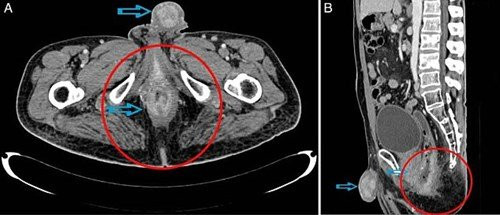

Ngay sau đó, ông được chuyển đến Viện nghiên cứu y học Jawaharlal, Puducherry, Ấn Độ tiến hành chụp CT. Kết quả chuẩn đoán phát hiện bệnh nhân có một khối u dài tới 10cm trong ống hậu môn. 1cm của khối u đã nhô ra khỏi hậu môn khiến bao quy đầu sưng lên.

Các bác sĩ tại đây cho biết, khối u đã di căn vào bàng quang, niệu đạo và đến đầu dương vật. Đây là biểu hiện của ung thư tuyến- một căn bệnh bắt nguôn từ khối u di căn trong dương vật và hậu môn.

các bác sĩ tại Viện nghiên cứu y học Jawaharlal, Puducherry, Ấn Độ đã tiến hành chụp CT. Kết quả phát hiện bệnh nhân này có một khối u 10cm trong ống hậu môn, trong đó 1cm của khối u đã nhô ra ngoài hậu môn. Họ cũng nhận thấy dấu hiệu sưng trên quy đầu.

Các bác sĩ cho biết, khối u đã di căn vào bàng quang, niệu đạo và đến đầu dương vật. Đây là một trong những dấu hiệu của ung thư tuyến, căn bệnh bắt nguồn từ một khối u hình thành từ các tế bào biểu mô của cơ thể.